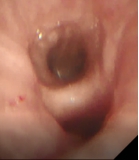

术前支气管 术中改变 术后支气管